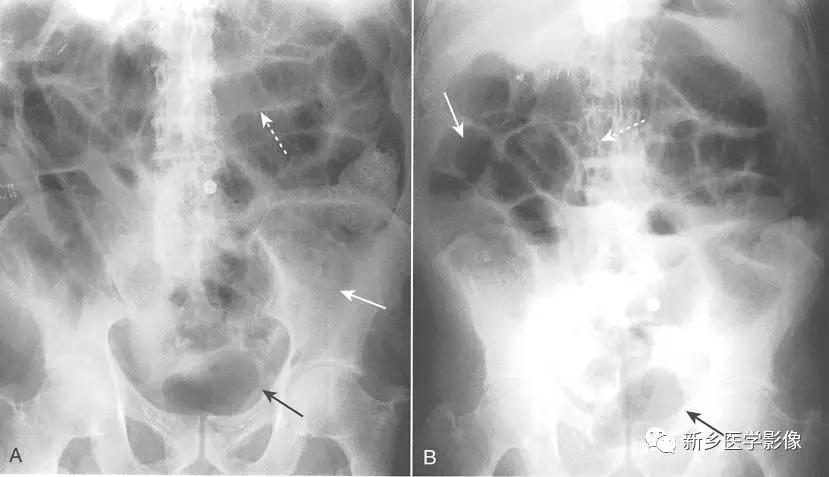

传统X线平片上,梗阻点近端可见多个扩张的小肠肠襻(>2.5cm)。

当肠 腔开始扩张,小肠肠襻逐一 堆积,形成阶梯状外观,一般由左上腹开始,随着疾病进展逐步向右下腹(黑色实线箭头)发展,具体范围及程度取决于小肠梗阻点有多远。

一般来说,若是近端小肠梗阻(例如近端空肠),则扩张的小肠肠襻数量较少;若是远端小肠梗阻(例如回盲瓣处),则扩张的小肠肠襻数量较多。

在直立位或侧卧位片上,在梗阻近端小肠通常可见多个气-液平面。

如果时间足够长,梗阻远端的肠道内容物可完全排出,则在结肠尤其是直肠内只有很少或完全见不到气体影。

在机械性小肠梗阻中,相对于塌陷的大肠,小肠往往表现为不成比例的显著扩张。